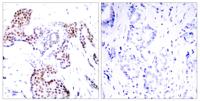

Specificity:Phospho-Elk-1 (S389) Polyclonal Antibody detects endogenous levels of Elk-1 protein only when phosphorylated at S389.

Dilution:WB 1:500 - 1:2000. IHC 1:100 - 1:300. Immunoprecipitation: 2-5 ug:mg lysate. ELISA: 1:10000.. IF 1:50-200